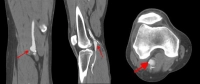

Filmbeispiel: Präoperatives CT-Angiogramm

Angiografia por TC

• complementa a ultrassonografia para o planejamento do manejo cirúrgico do AAP